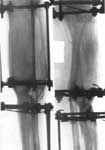

1.Results of traffic accident.

2.Defect after removal of medium/third of thing-bone.

3.Replacement of defect (24 centimeter) by means of Ilisarov's apparatus.

4.Results of treatment.